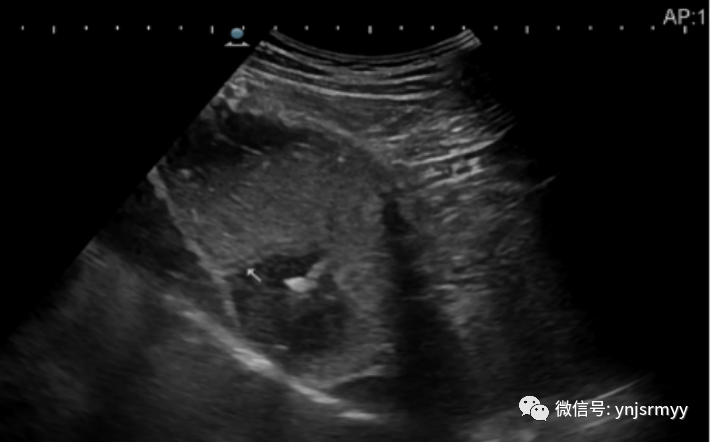

急性胃炎

什么是260胃镜胃肠不适,不想做胃镜,建水县人民医院胃肠超声造影检查能看!_https://www.jmylbn.com_新闻资讯_第16张